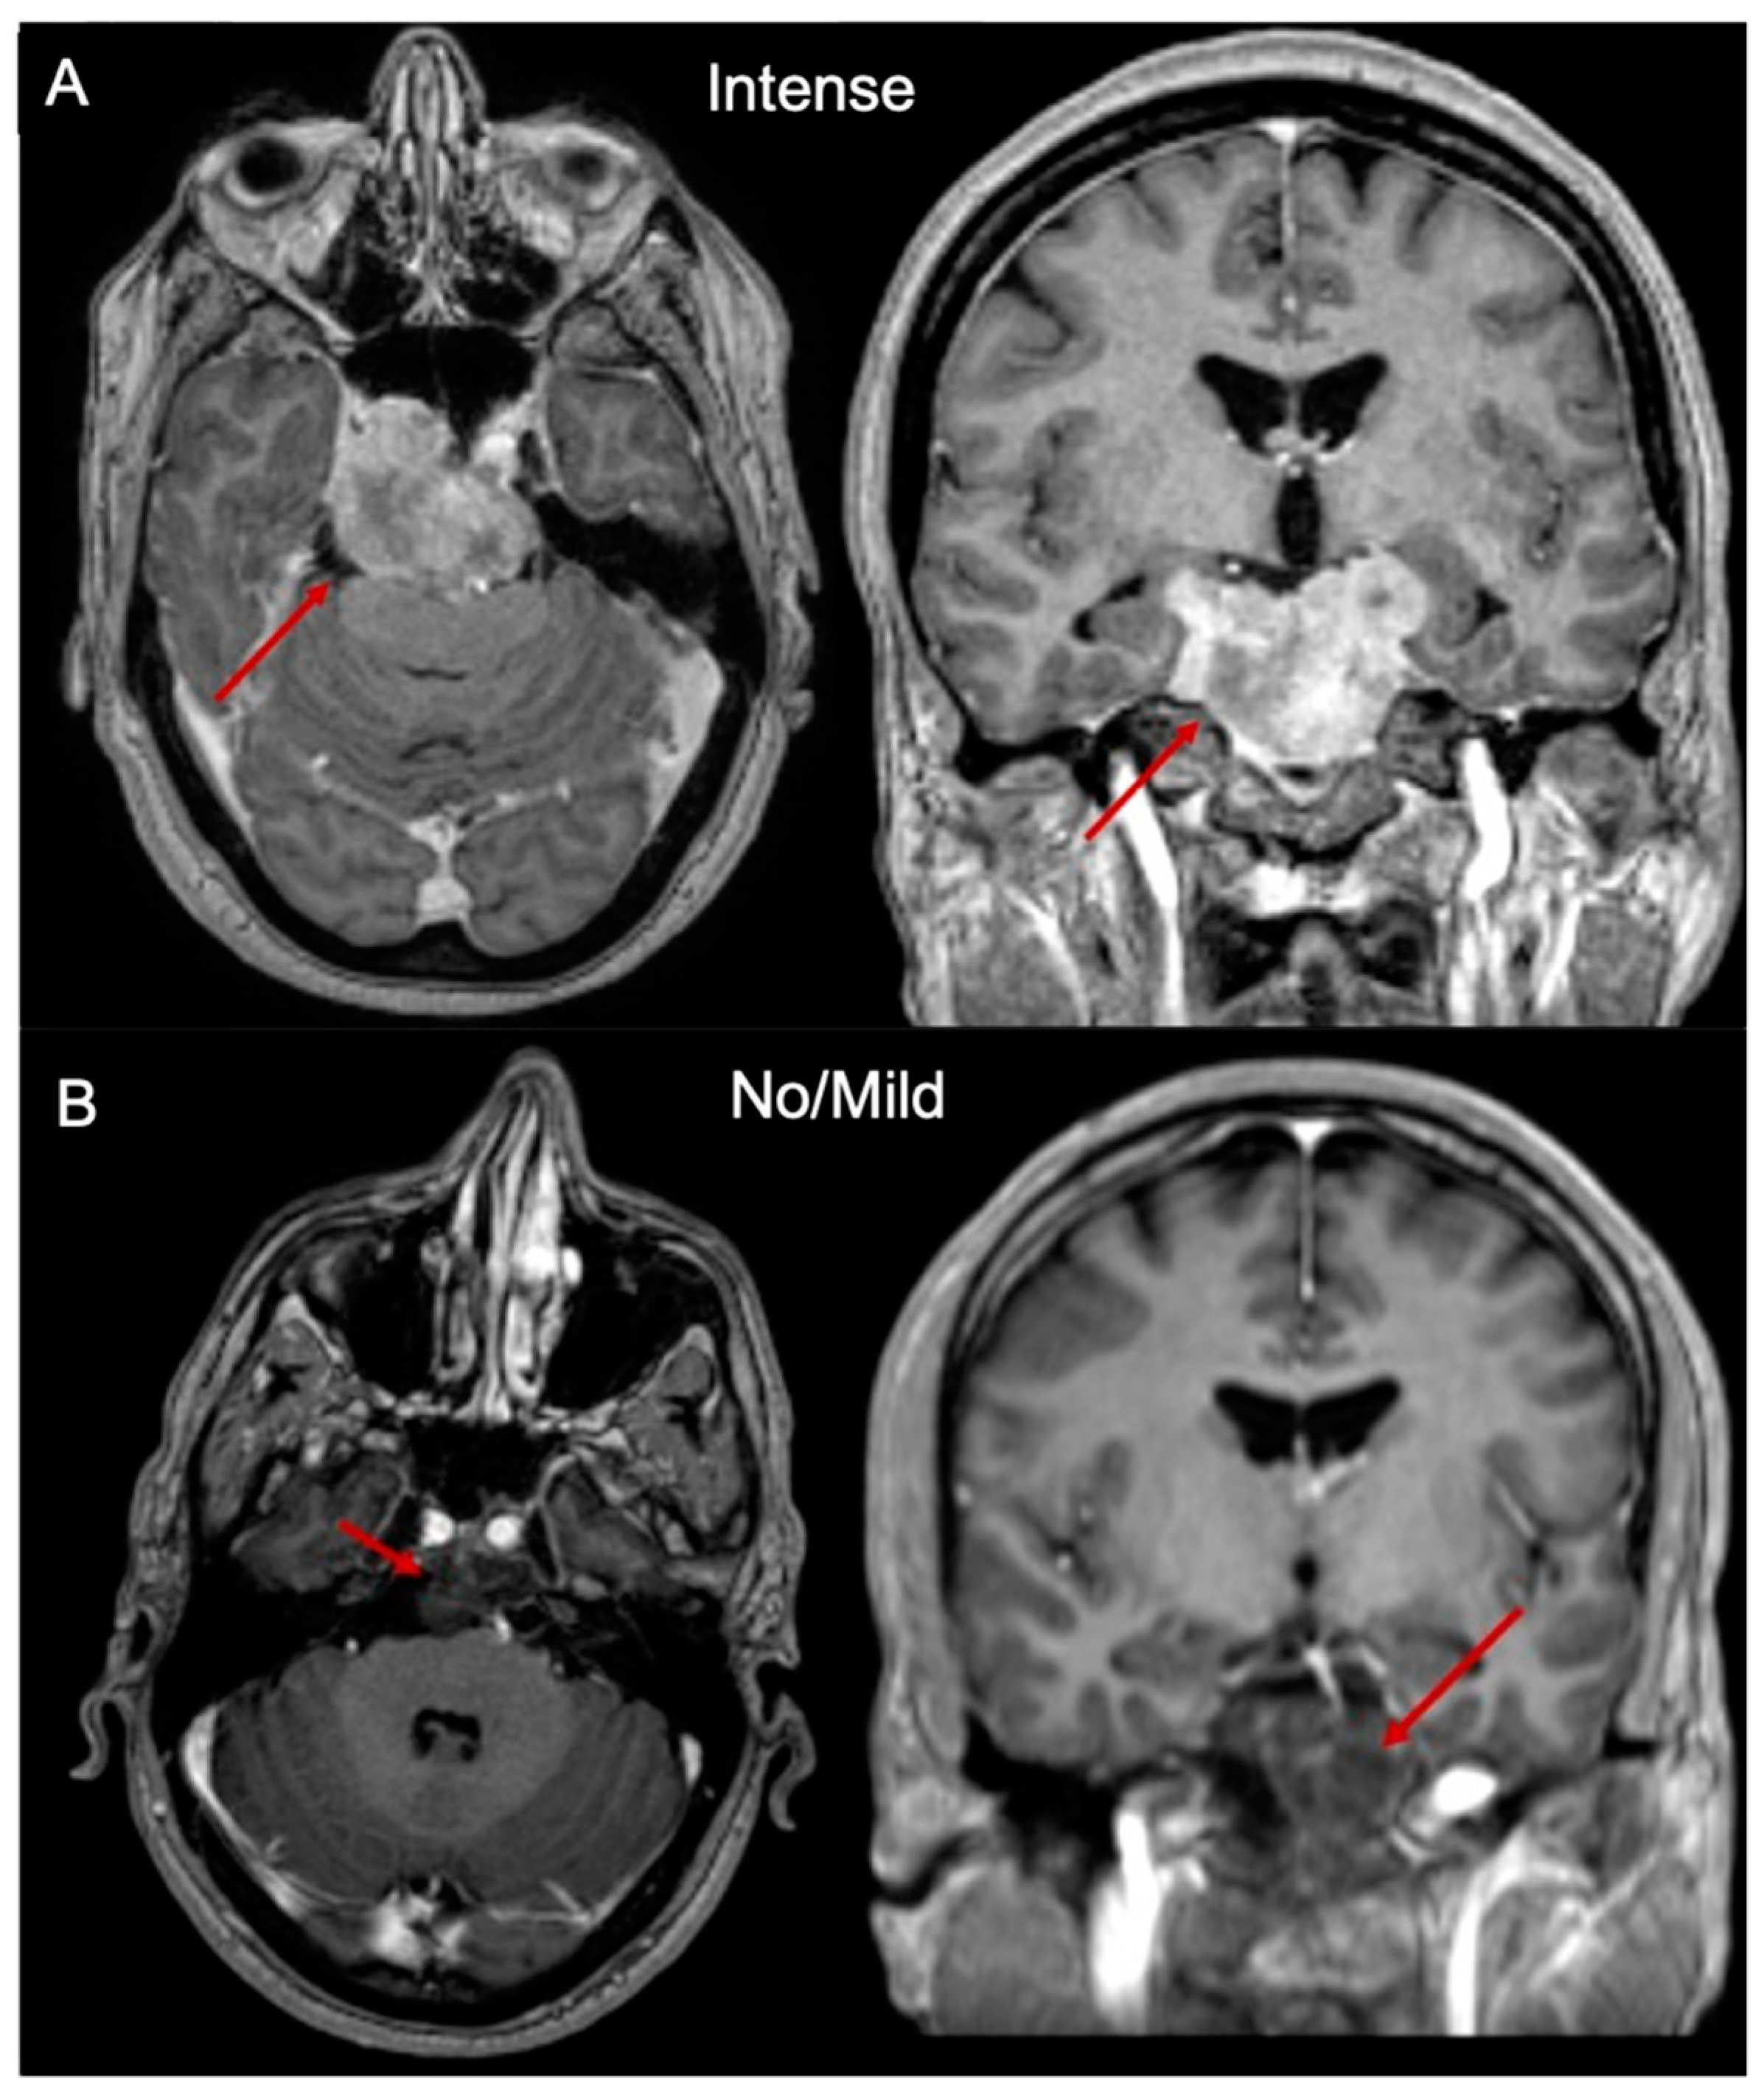

2.3. Sphingolipids Characterization and MR Contrast Enhancement Pattern